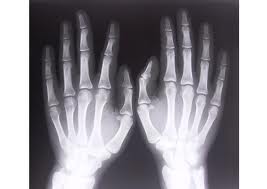

![]() | Rentgenstarus izmanto medicīnā, lai apskatītu, vai nav lauzti kauli, lai noteiktu dažādas slimības. Rentgenstarus izmanto arī ļaundabīgo audzēju ārstēšanā. Parasti rentgenstarojuma deva apskatē ir neliela un blakus parādības neizraisa. Tomēr ir zināms, ka ilgstoša vai spēcīga šo staru iedarbība uz organismu rada smagas slimības. Tāpēc rentgenstarojumu izmanto tikai nepieciešamības gadījumos, tos neiesaka lietot sievietēm, kas gaida mazuli. Veicot rentgena apskati, citas ķermeņa daļas apsedz ar svina pārklāju. Tas nelaiž cauri rentgenstarus. |